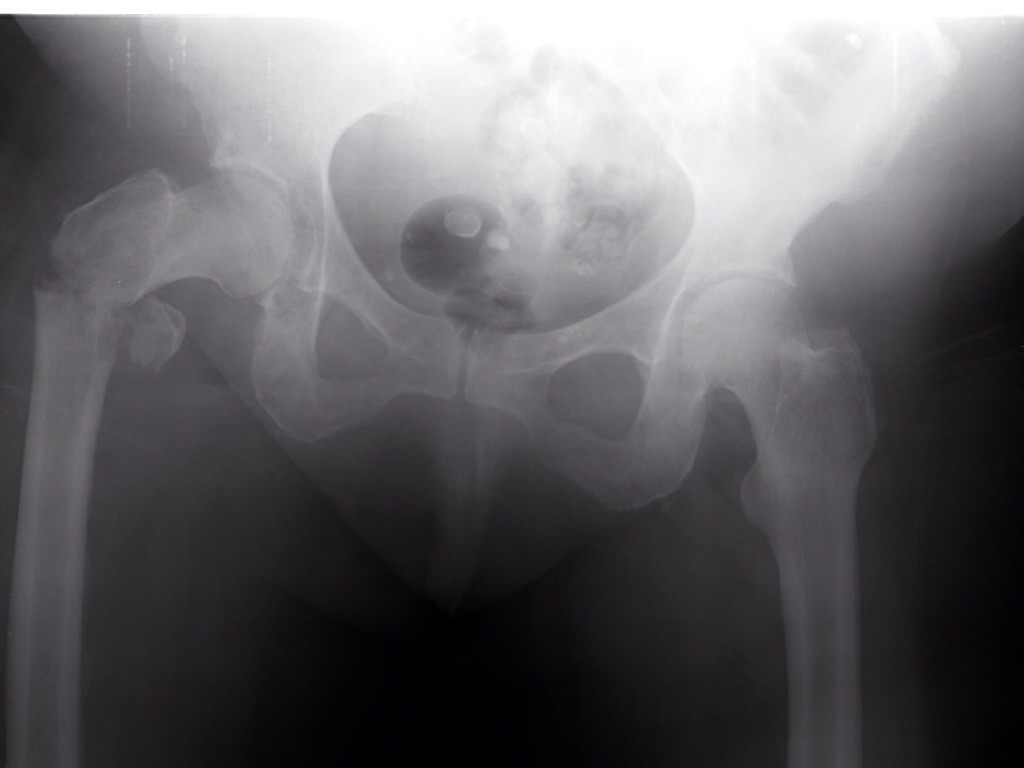

GROWTH PLATES